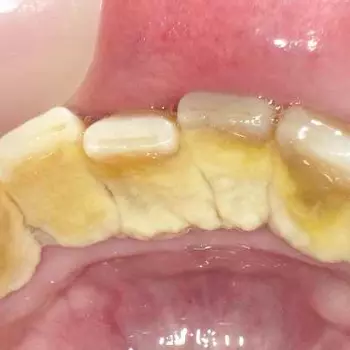

치석 이란, 치구(플라크)와 타액에 포함된 인산이나 칼슘, 음식물 찌꺼기 등이 결합해 치아에 달라붙어 석회화된 것입니다.

치석은 약 80%가 인산칼슘이고 그 외에 단백질이나 탄수화물, 세균의 시체, 음식물 찌꺼기 등이 포함되어 있습니다.

치석은 이름처럼 돌처럼 단단하므로 일반 칫솔질로는 제거가 불가능하며, 치석을 제때 제대로 제거하지 않으면 증상이 악화되어 치은염이나 치주염으로 발전될 수 있으니 적절히 케어해야 합니다.